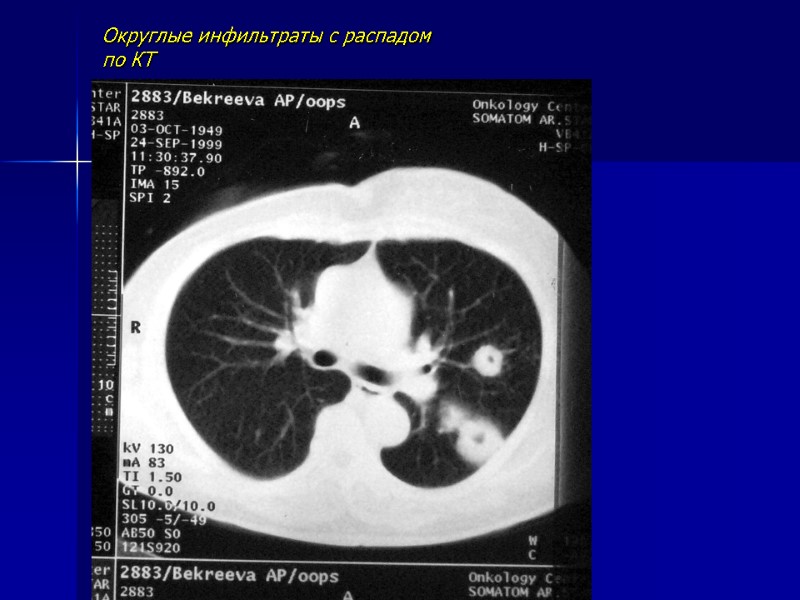

Округлые инфильтраты с распадом по КТ